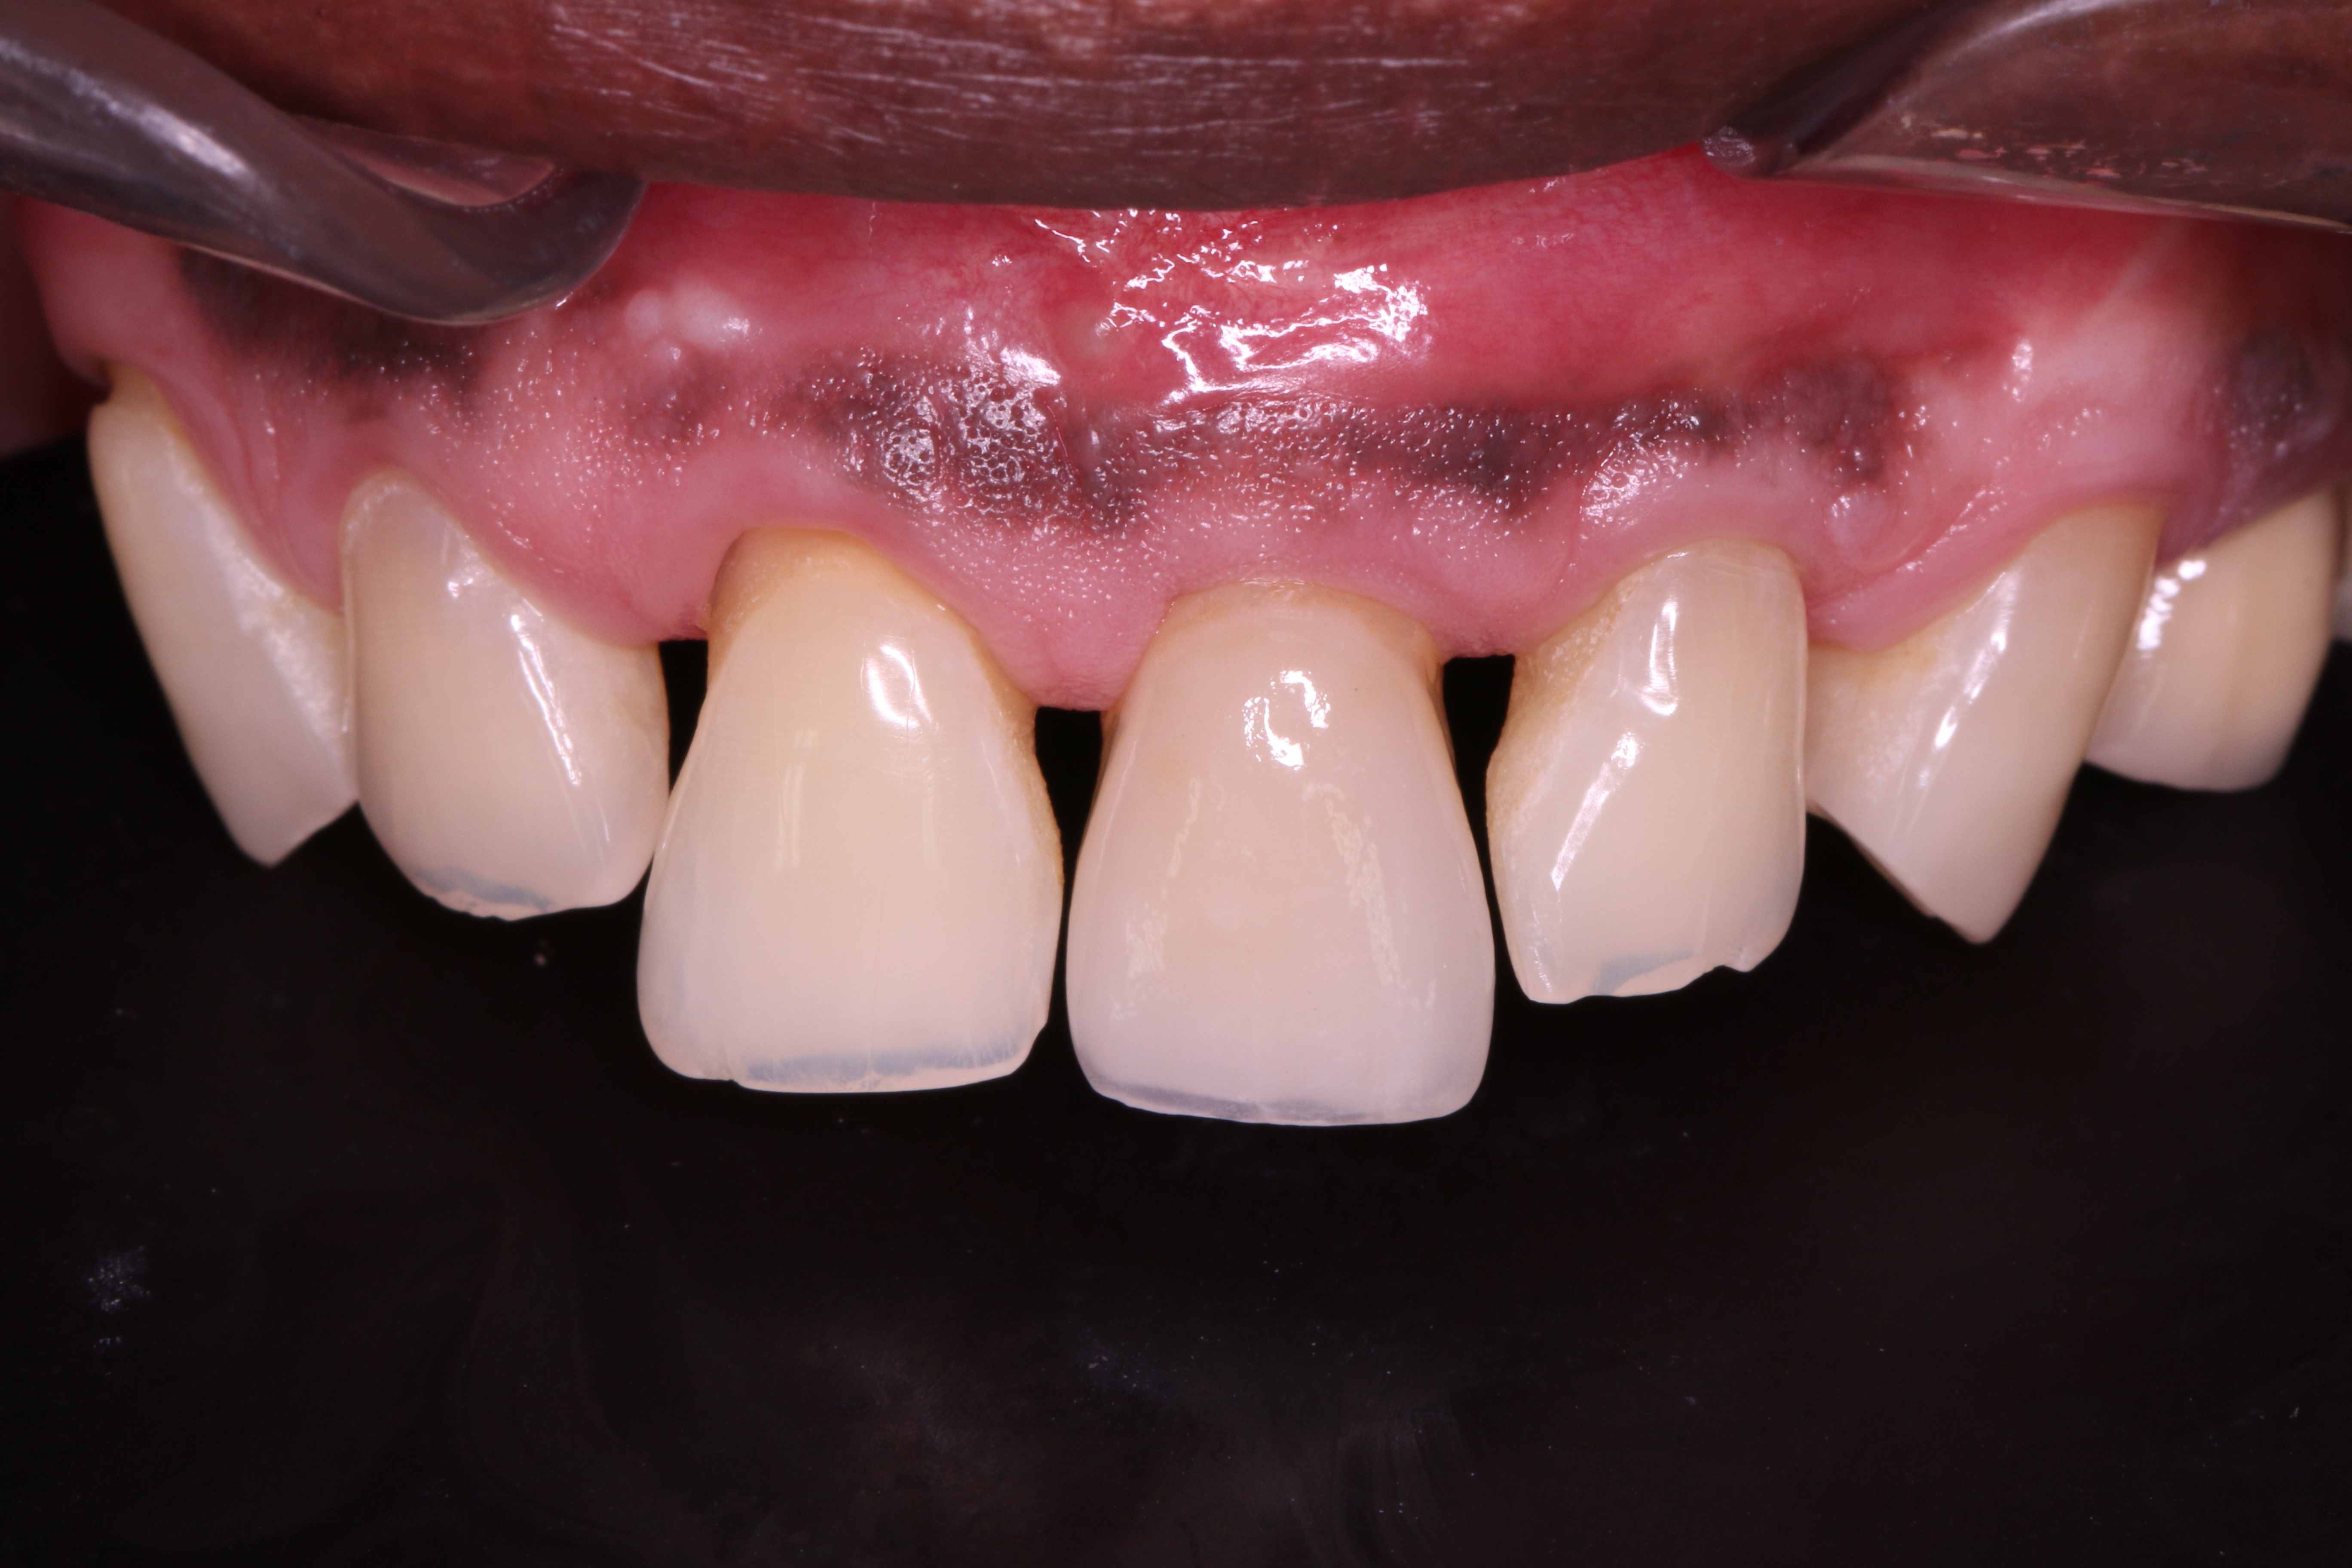

13/19 - Placement of a temporary fixed adhesive Rochette

GBR with cerabone® and Jason® membrane in the front tooth region - Dr. H. Maghaireh